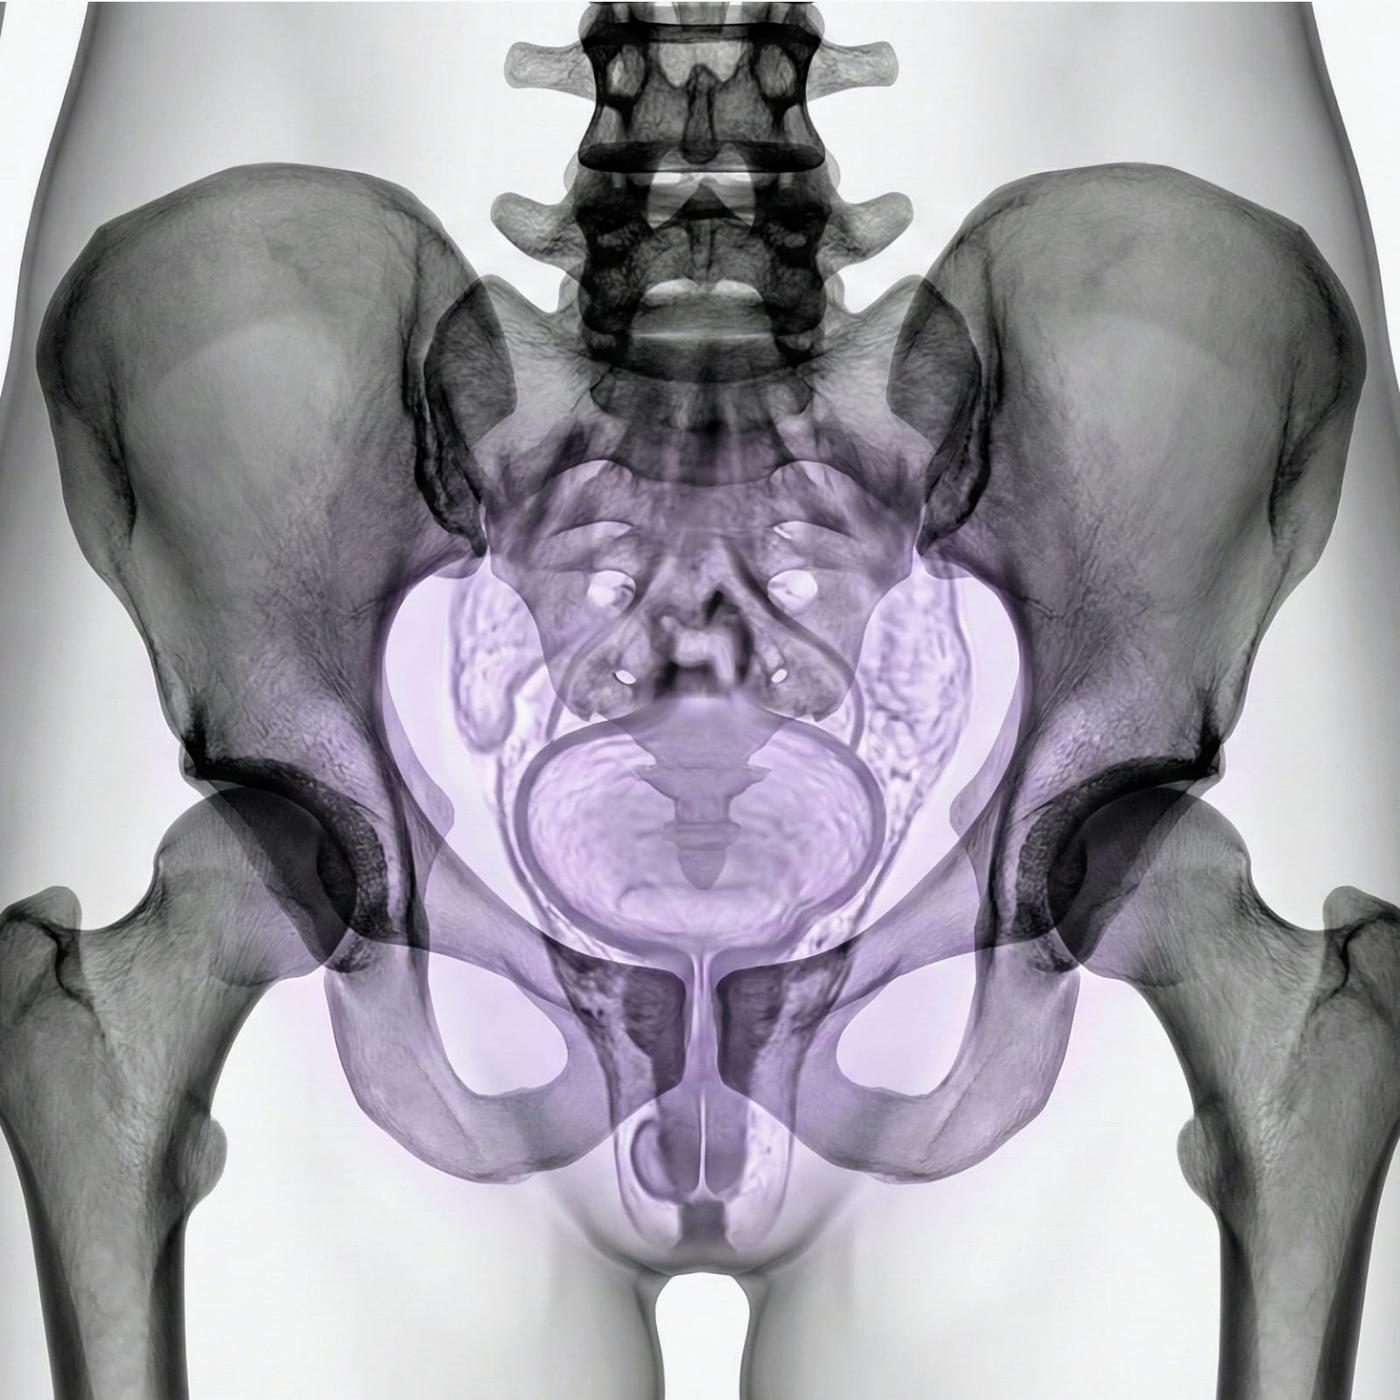

MRI Pelvic – for gynecological problems, cysts or suspected endometriosis

If you have pain in the lower abdomen, irregular bleeding, fertility problems or suspect that something is not right in the lower abdomen, an MRI examination of the pelvis can be the next step to get the right diagnosis. MRI pelvic, also called MRI gynecology, is a painless and radiation-free examination that provides very detailed images of both the uterus, ovaries and fallopian tubes.

The examination is used when other methods such as ultrasound or gynecological examination have not been able to explain your symptoms. With the help of MRI, conditions such as endometriosis, fibroids, cysts, tumors, malformations or effects on nearby organs such as the bladder or intestines can be detected. It is also an important method before fertility treatment or in preparation for surgery.

Whether you are seeking answers to long-term symptoms or following up on previous findings, pelvic MRI gives you and your doctor a clear picture that can form the basis for the right treatment and continued care.